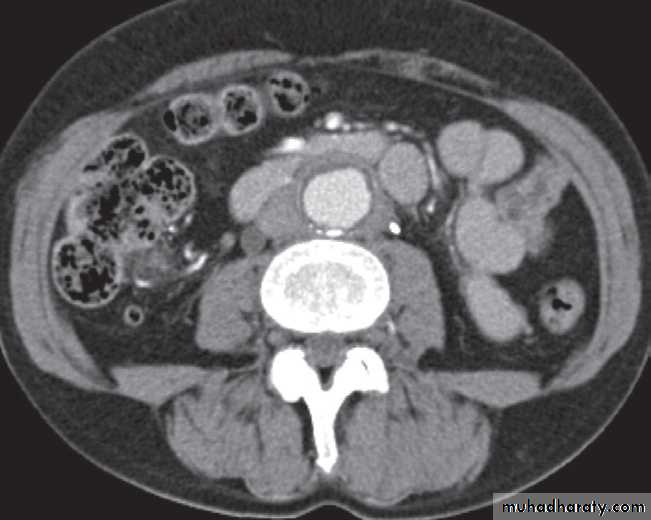

Computed tomography is now widely used to evaluate urinary tract obstruction .In acute obstruction, non-contrast enhanced CT sensitively demonstrates calculi and the unopacified, dilated collecting system can frequently be traced down to the point of obstruction .

Non-contrast CT is often used in acute ureteric colic, as an alternative to IVU, in patients with an allergy to intravenous contrast medium.